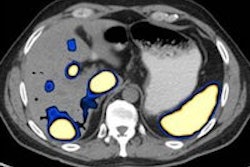

In the abdomen, molecular imaging (MI) has become synonymous with FDG-PET, but important applications are now starting to emerge.

MI is enhancing assessment of therapy response and facilitating risk-adapted, personalized therapy, and research on exploiting the specific molecular features of tumors, and their microenvironment will eventually translate into better future clinical care, attendees learned at the 2013 European Society of Gastrointestinal and Abdominal Radiology congress in Barcelona. Click here to find out more.